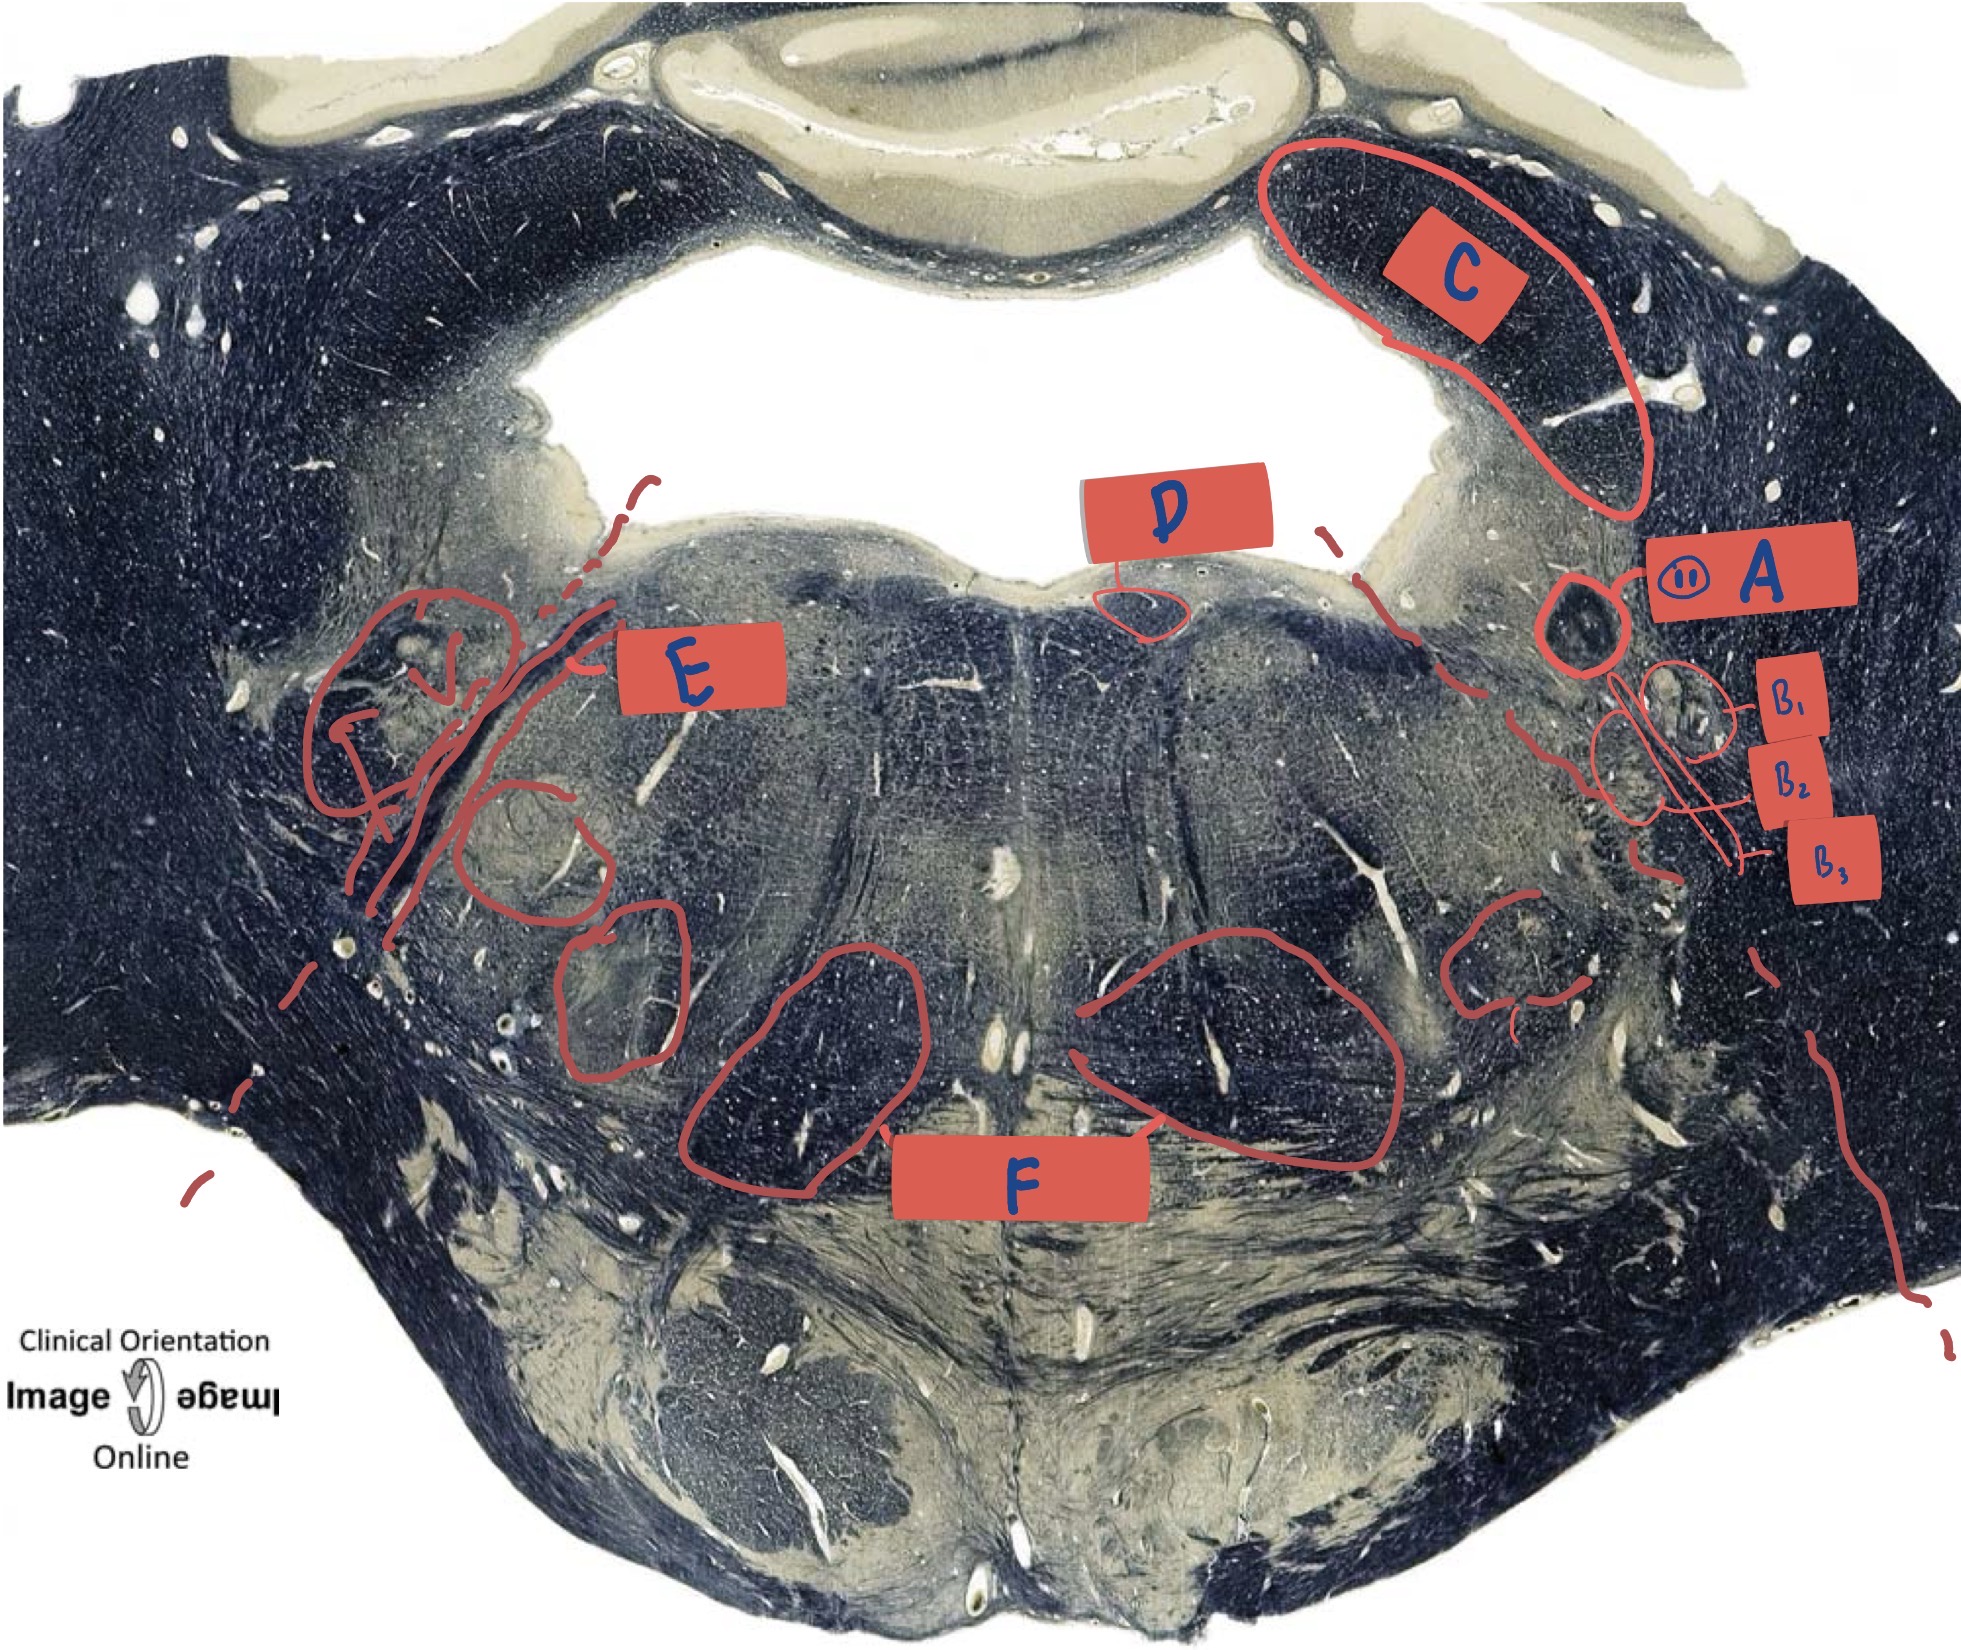

What is A?

Sulcus limitan

What is B?

Hypoglossal nucleus

What is C?

Dorsal motor nerve of Vagus

What is D?

Medial vestibular nucleus

What is E?

Solitary nucleus

What is F?

Medial longitudinal fasciculus

What is G?

Nucleus ambiguus

What is H?

Medial lemniscus